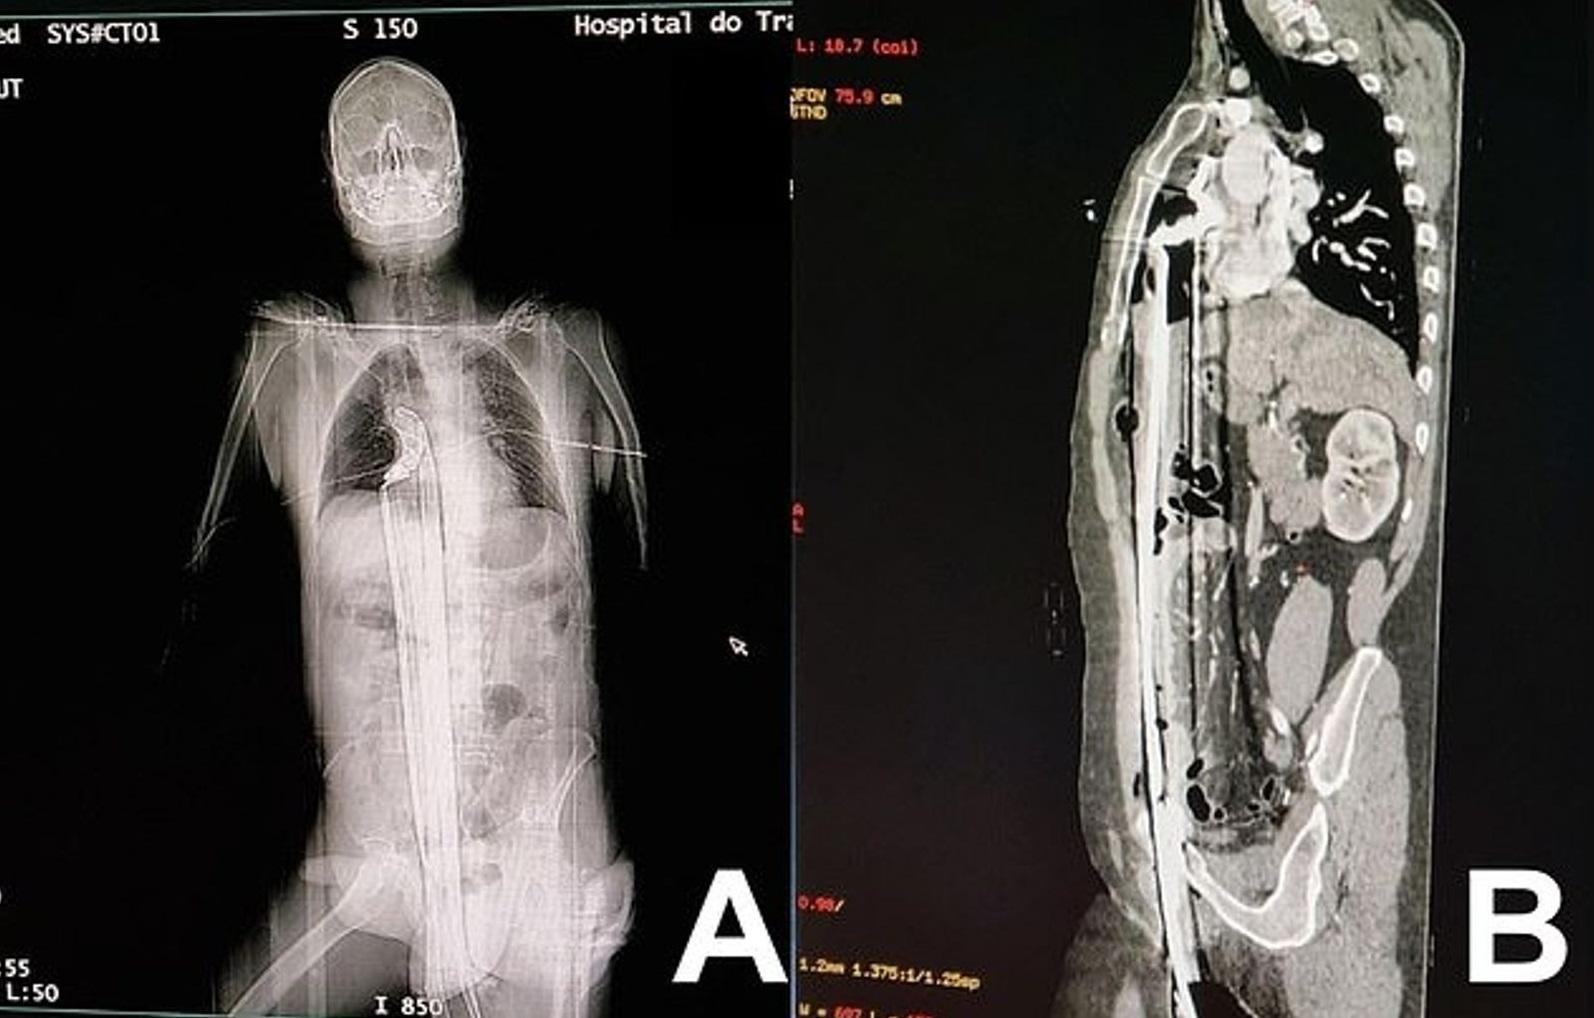

掃描圖像顯示,長鋼條從男子下體插進體內,直到肺部下方。(互聯網)

巴西醫生團隊近日在《國際外科手術病例報告期刊》發表罕見病例,一名57歲男子被一條長約91厘米(約2.98英尺)的鋼條,從下體插入、貫穿到肺部,危險狀況看來會致命,但男子竟奇蹟生還。

醫生指,該名男子被長約91厘米的鋼條,從下體插入並貫穿上半身,插到肺部與橫隔膜附近位置,肝臟被穿刺,所幸避過心臟。男子被送院急救,醫生初步檢查發現,其心率、血壓和血氧狀況,出奇地都正常。

醫生當時判斷,男子有生命危險,於是立即動手術。剖腹後,醫生將部分胸骨切開,從體內取出鋼條後,再縫合腹部。